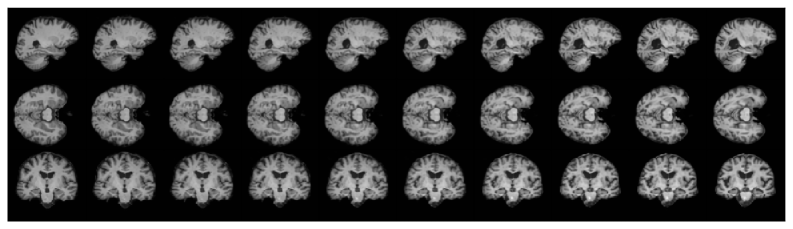

Refer to caption

Figure 2: Interpolation using a latent diffusion model similar to (Pinaya et al., 2022) with our proposed method. Each row represents different slices of the brain. The interpolation shows the generative transition between a healthy brain (left) and a brain with Alzheimer disease (right). We show in Section 4 that we obtain a lower Fréchet inception distance (fid) compared to other interpolation schemes.

In this paper, we propose a general framework for interpolating in generative models. We consider interpolation analogous to computing a geodesic main support of any given (learned) data distribution providing a trade-off between the smoothness of geodesics and high-density regions (Fig. 1). We introduce a novel algorithm for computing these curves and prove that our algorithm converges to a local minimum and has local quadratic convergence. Further, we show that along the optimal curve, our approach can be seen as a geodesic under a regularized Riemannian metric. Our interpolation approach is applicable to a wide array of generative models. Empirically, we demonstrate it on variational autoencoders, diffusion models, and Riemannian diffusion models, and we show that it obtains curves with a higher likelihood for different models and datasets compared to baselines.